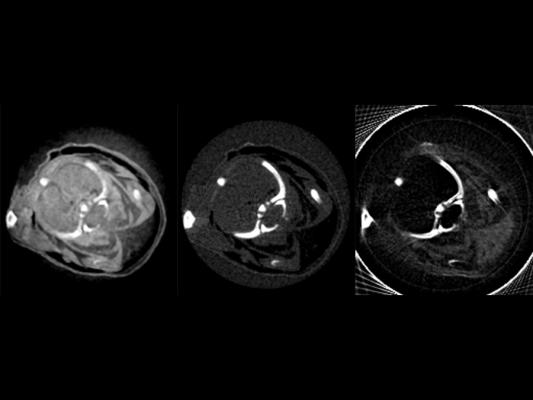

The scientists inserted an optical grating into the focused X-ray beam, allowing them to detect even the tiniest phase shifts and scattering of the radiation in addition to the absorption of X-rays. The first phase contrast tomography image from a compact synchrotron source was successfully acquired.

The phase contrast, dark field and absorption images made using the new technology have complementary properties. Liquid in tissue that remains indiscernible and, thus, invisible using conventional X-ray tubes, suddenly comes to life. The greatly improved soft tissue contrast of the new X-ray technology could also help make tumors detectable earlier on and enable quick diagnoses – in medical emergencies, for example.

The clarity of the new technology becomes apparent when comparing white and brown fatty tissue. “In a mouse we were able to recognize not only heart, liver and other organs much better, but could even differentiate between brown and white body fat,” said Eggl.